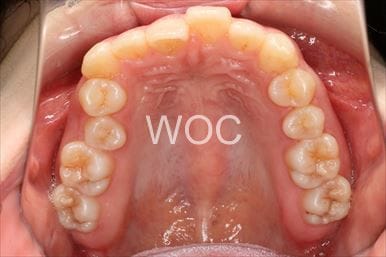

治療前1

治療後1